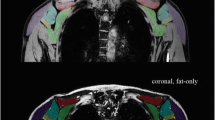

Volume of interest (VOI)–based analysis

Supraspinatus (SSP), subscapularis (SSC), and infraspinatus (ISP) were manually segmented on the opposed-phase Dixon sequence along the muscular borders by one trained radiologist (3 years of experience in musculoskeletal radiology, Fig. 1). Tendinous structures and the investing fascia were carefully excluded from segmentation. VOIs were subsequently overlaid on FF maps and on the b = 0 images to approve correct alignment. DMI-derived parameters and FF were extracted from the VOIs.

Quantitative MR imaging

Quantitative image parameters were successfully calculated in all subjects (an exemplary case is depicted in Fig. 2). Mean FF for the SSP was 18.5% ± 19.8%, for the ISP 5.8% ± 10.7%, and for the SSC 5.7% ± 11.3%. Although FF was lower in males as compared to females for all analyzed RC muscles, the difference was not statistically significant (mean of all muscles was 6.3% ± 10.3% in males vs. 12.5% ± 18.6% in females, p > 0.05; see Table 1).

Detailed descriptives of the microstructural DMI parameters V-intra, V-extra, and V-ISO are displayed in Table 1. V-intra was significantly higher in all RC muscles of male compared to female subjects (in contrast, V-ISO was significantly lower in the respective RC muscles of male participants compared to females). No statistically significant sex difference was found for V-extra (all p > 0.05). Please see Fig. 3 for some exemplary cases.

Quantitative DMI parameters of the SSC and ISP in an exemplary male (left column) and female participant (right column). V-intra (A, B) was higher and V-ISO (A’, B’) was lower in all RC muscles in male (left column) compared to female subjects (right columns). Calculated V-intra (A, B) and V-ISO (A’, B’) color maps overlaid onto the water image of T1w Dixon. Cold color indicates low, and hot color indicates high values